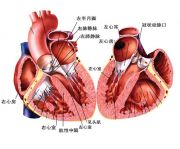

| 2021年7月26日 (一) 20:03 | 心脏解剖图.jpg (文件) |  |

79 KB | Uploaded with SimpleBatchUpload | 3 |